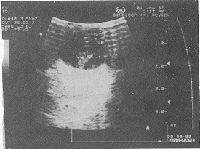

彩色多普勒超声检查结果:二例声像图类似,眼球径线正常,玻璃体透声差,二例均可见于晶体后缘至眼底的倒三角形中强回声团,尖端与视乳头相连,底部与晶体后缘相连(图1),例1近晶体处回声略低,随眼球转动,视网膜回声正常;视网膜中央动脉彩色多普勒血流正常。例2视网膜中央动脉彩色血流显示欠清,血流速度减慢。彩色多普勒超声诊断:Cloquet氏管肌性纤维化增生。

图1 视乳头至晶体后缘倒三角形中强回声团